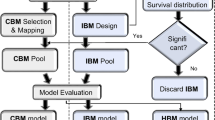

Radiomic feature selection

Following recommendations [18], radiomic features were pre-selected based on previous published studies. This obviated data-driven feature selection thereby reducing the risk of data overfitting. Published studies were evaluated using the ‘Transparent reporting of a multivariable prediction model for individual prognosis’ (TRIPOD) [19] and ‘Radiomics Quality Score’ checklists [20]. Identifiable Image Biomarker Standardisation Initiative features were sought [13].

Of the identified published studies [11, 12, 21, 22], features proposed by Piazzese et al were excluded as the interpolation strategy employed (2 mm isotropic) would have resulted in a significant reduction of the axial image resolution [11]. Features proposed by Larue et al were excluded as they evaluated nonlinear effects in a high-dimensional feature set using a random forest method, complicating the extraction of a few individually informative linear predictions [12]. Zhang et al achieved a high TRIPOD score of 30 [21] and examined a limited number of previously proposed predictors, each of which was identifiable; thus, these features were extracted—GLCM_Contrast, GLCM_Correlation and GLCM_InverseDifferenceMoment. Furthermore, GLCM correlation was independently identified as a predictor of response in Klaasen et al [22]. Following Peduzzi and Concato’s guideline recommendation of more than 10 events per modelled feature [23], an unsupervised method was applied to identify the most suitable two of the three proposed features. The most collinear GLCM feature with respect to tumour volume and the other GLCM features was excluded.